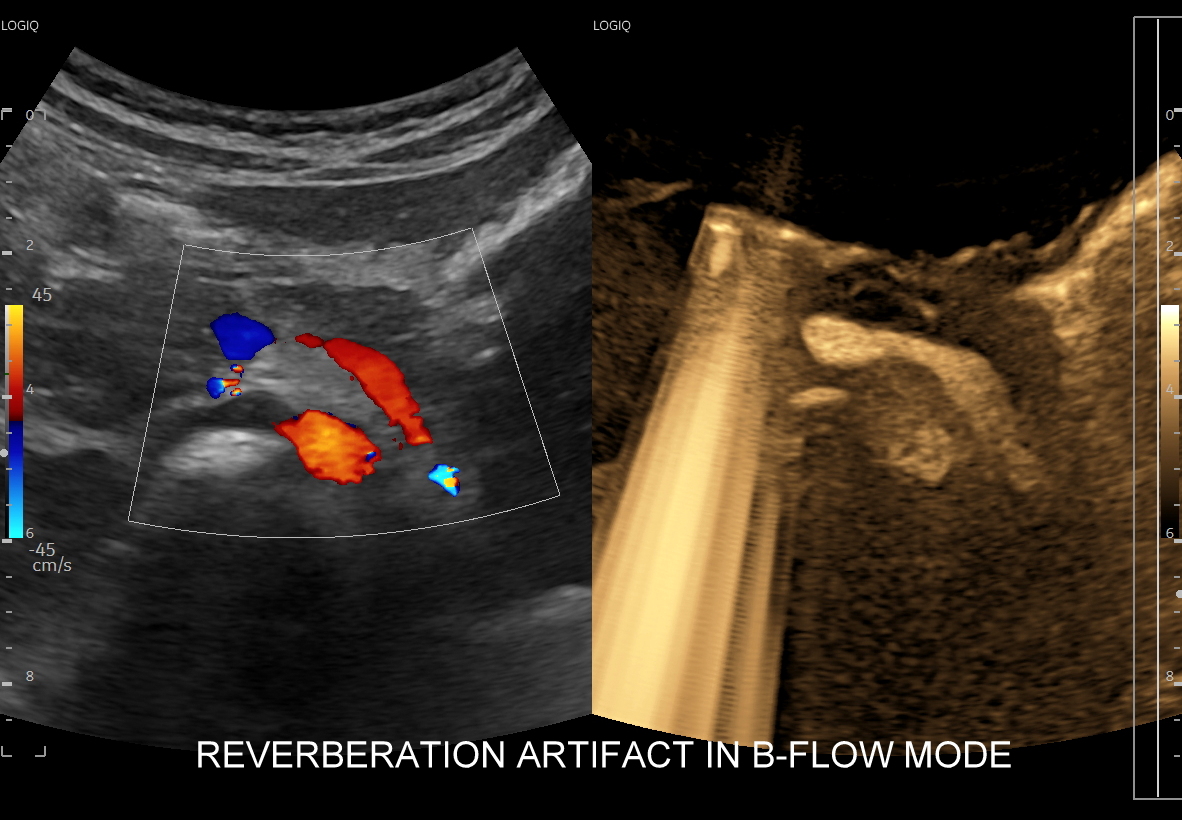

Omawiana modalność nie jest oparta o fizyczne zjawisko Dopplera. W związku z tym nie jest zależna od kąta poruszającej się krwi (!), nie dostarcza informacji o prędkości ani o kierunku poruszania się skanowanej tkanki; nie obserwuje się w niej również typowych dla Dopplera artefaktów w postaci aliasingu, szumu oraz rozkwitania (blooming). Z kolei podobnie jak w podstawowej prezentacji czarno-białej (tryb B) w prezentacji B-flow występują artefakty oparte o zjawisko rewerberacji.

Tryb B-flow wyjątkowo korzystnie sprawdza się także przy badaniu wnętrza dużych i średnich naczyń. Otóż umożliwia on pewne zobrazowanie drożności naczynia, umożliwia wykazanie obecności / lokalizacji naczynia przy niesprzyjających warunkach obrazowania w trybie B, a poza tym uzyskiwane w omawianym trybie obrazy zarysów błony wewnętrznej naczyń (np. tętniczych blaszek miażdżycowych, skrzeplin przyściennych, zmian w przebiegu dysplazji włóknisto-mięśniowej, czy zapaleń tętnic) charakteryzują się wysoką rozdzielczością i kontrastowością. Skany dużych naczyń w trybie B-flow przypominają wręcz te uzyskiwane w klasycznej angiografii opartej o promieniowanie rentgenowskie. B-flow wykorzystywany może być praktycznie i rutynowo do obrazowania naczyń szyi i kończyn, naczyń wątroby, naczyń trzewnych, nerkowych oraz dużych naczyń brzusznych.